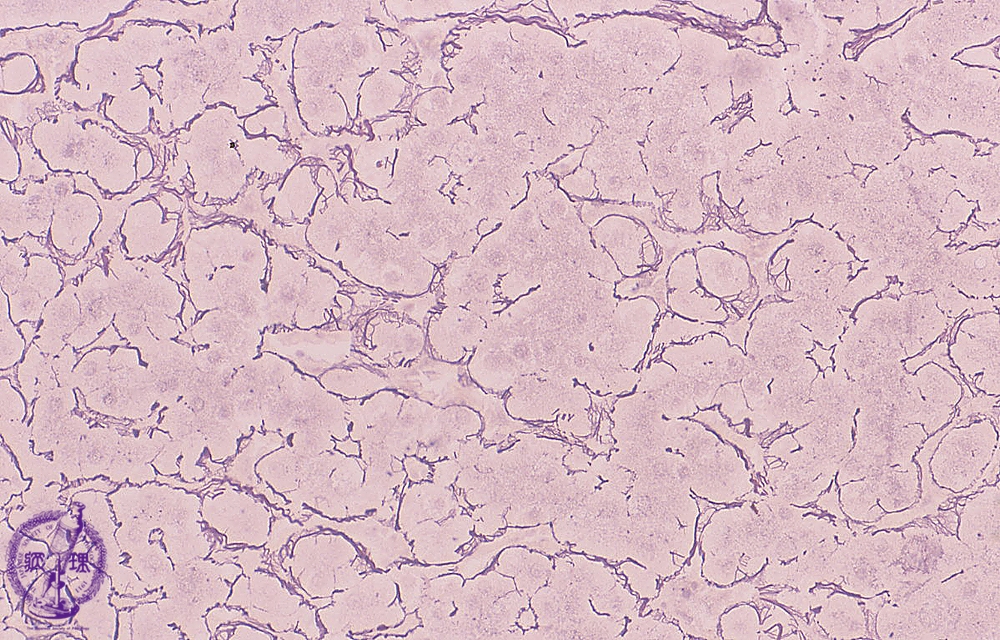

Microscopic image (silver stain, intermediate power): Regenerative nodules show architectural disruption with hepatocellular plates composed of multiple (2-4) layers (normally 1-2 layers).